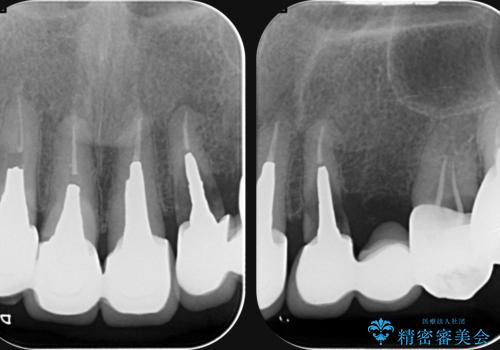

クラウン・コアを除去したところ支台となる歯は破折し残すことが難しい状況でした。

抜去を行ったのち、インプラント治療を計画しますが骨量が少ないため、まず骨の造成を行ったのちインプラントを埋入していく治療計画としました。